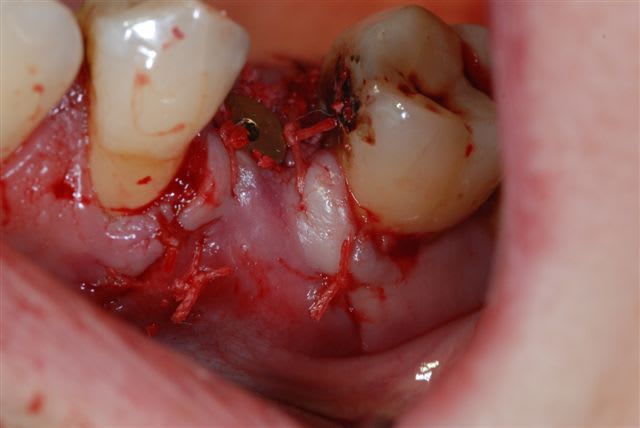

suite de la prémolaire fracturée: extraction , mise en place d'un implant tekka diametre 4 longueur 15 mm pour aller chercher un bon ancrage primaire. Il y avait 2 mm d'espaceentre l'implant et la corticale en vestibulaire et 1 mm en palatin, j'ai comblé au bio-oss et tracté la muqueuse sans tensions pour le recouvrir.

pas de photos du bio-oss en place car assistante absente et donc galère pour prendre la photo à ce stade.